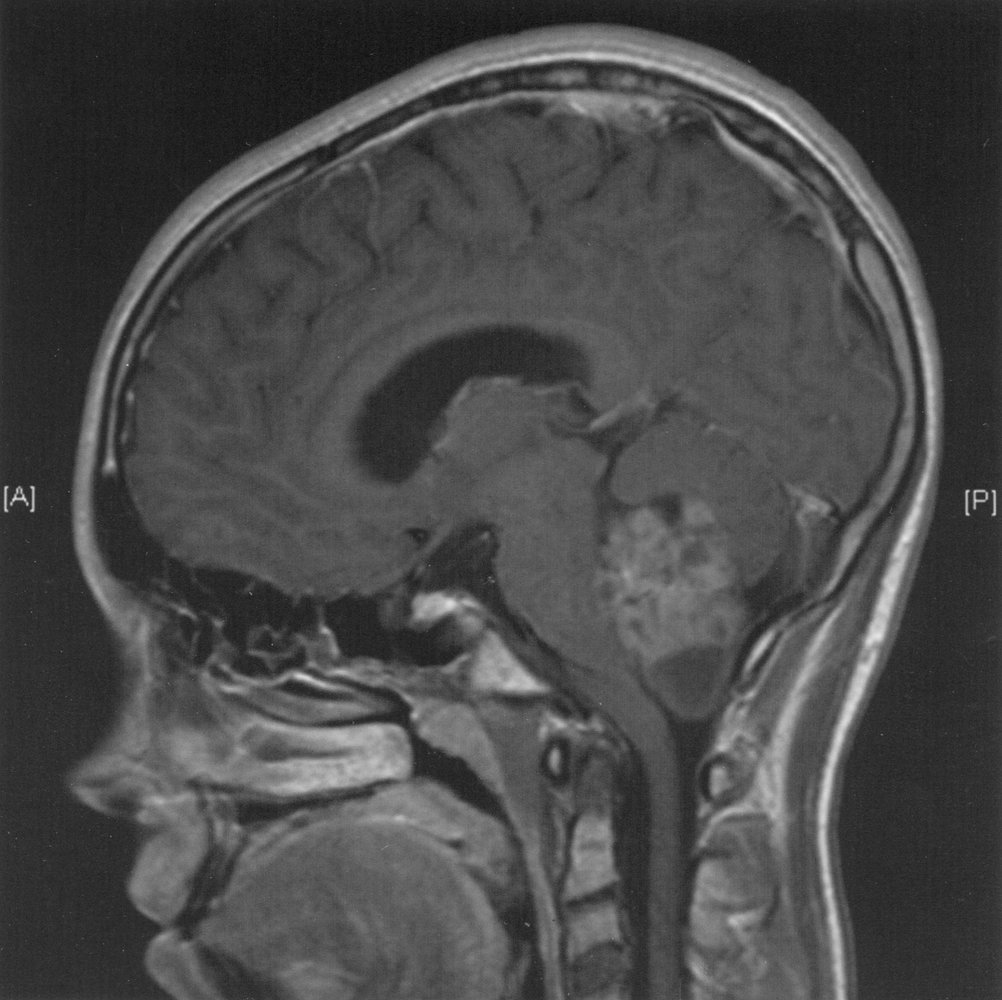

Pituitary adenomas are generally divided into three categories dependent upon their biological functioning: Pituitary adenomas signs and symptoms. Craniopharyngiomas are dysontogenic tumors with benign histology and malignant behavior.

Are potential complications of pituitary adenomas if there is compression of the central satiety center of the hypothalamus. Come join the discussion about schools, exams, news, prep. Typically, craniopharyngioma were of adamantinomatous type, occurred simultaneously to pituitary adenoma, presented with headache and visual loss, and affected men. No case of clearly documented metachronous lesion affecting a woman after pregnancy had been described before.